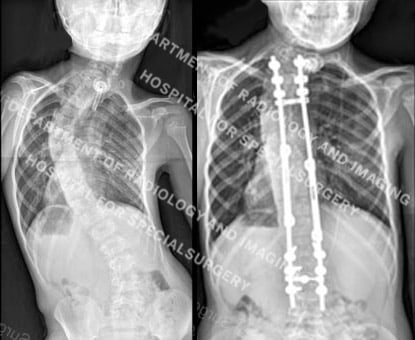

Figure 3. Posteroanterior (back-to-front) X-ray images showing a spinal curve in excess of 40° and then the same patient undergoing treatment with growing rods.